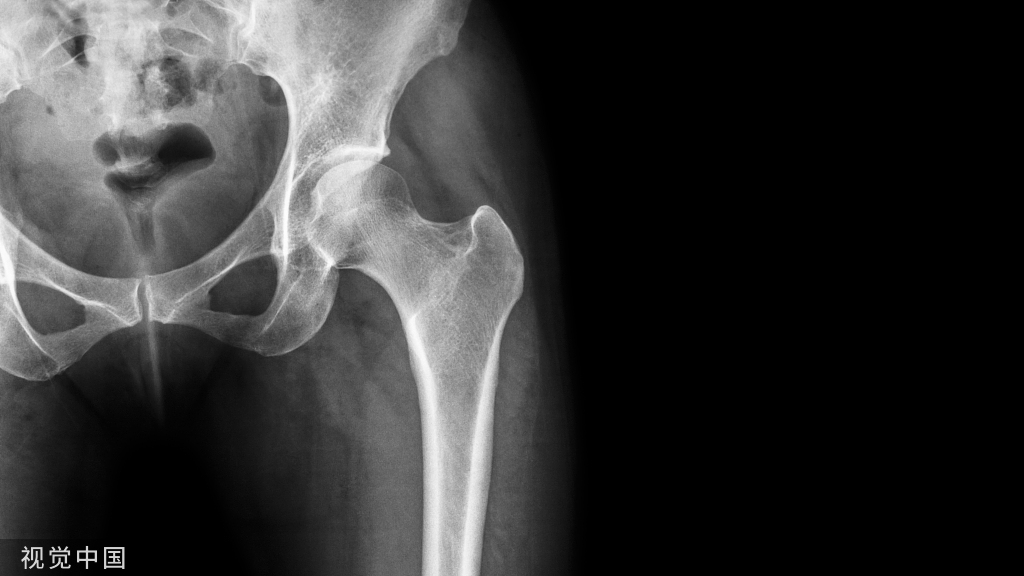

病例44,股骨转子间骨折,克氏针临时固定